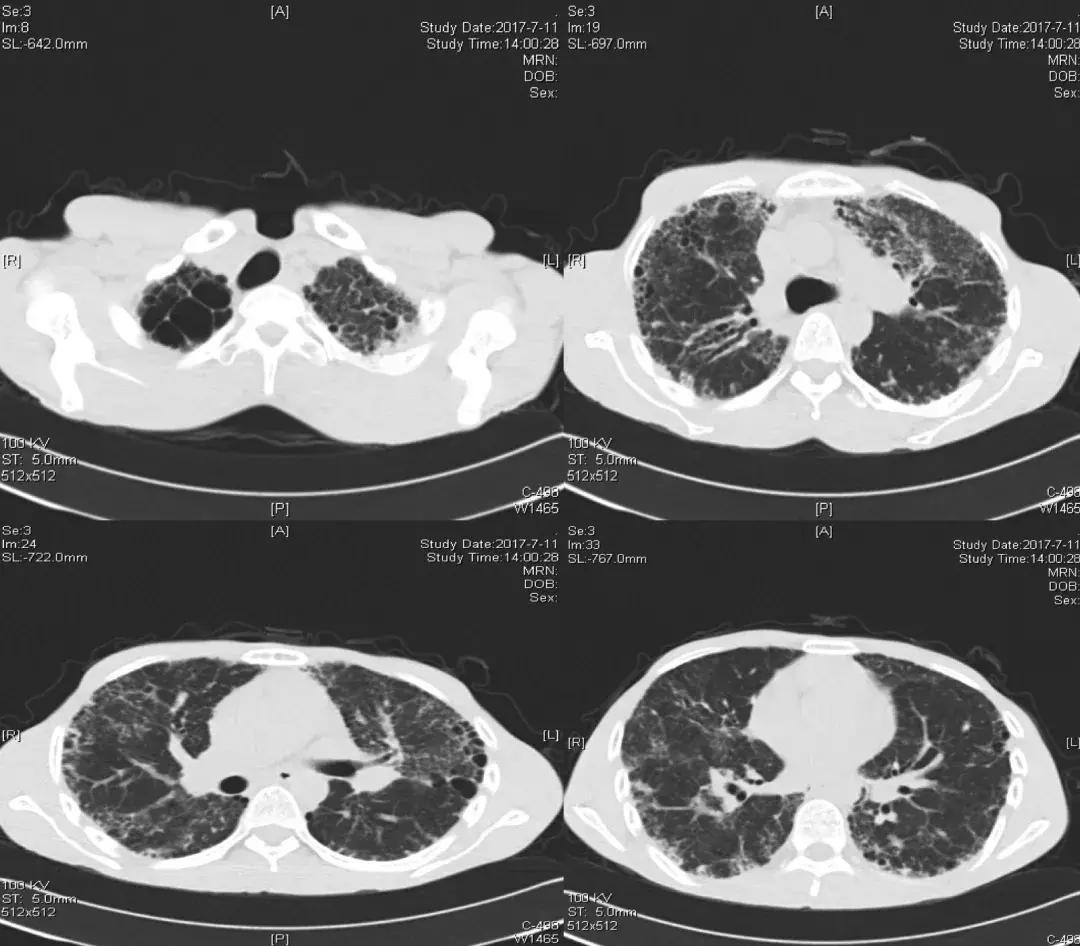

胸部CT(2017-07-11):

胸部CT(2018-02-22):